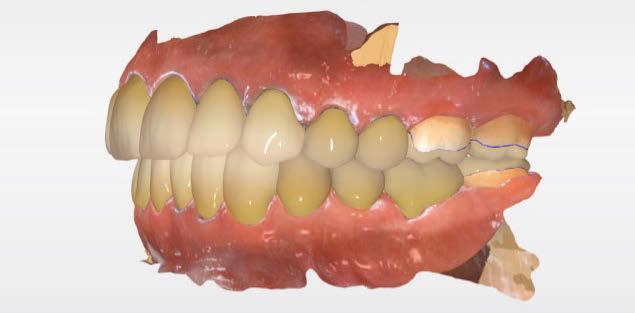

Acude a la consulta un paciente masculino de 35 años exigiendo cambios en la estética de sus dientes. El examen intraoral clínico y fotográfico reveló pérdida de estructura dentaria con facetas de desgaste en dientes anterosuperiores e inferiores, acentuándose hacia zonas oclusales de dientes posteriores.

El diagnóstico evidenció que el paciente presentaba alteración en la dinámica de la guía anterior por el desgaste de los bordes incisales, con pérdida de dimensión vertical oclusal (VDO), alteración del plano de oclusión y relaciones interoclusales inestables (Figuras 1 y 2)

Se obtuvieron modelos de estudio (Figuras 3-6) digitales mediante un escáner confocal de luz azul estructurada (PrimeScan, Dentsply Sirona) y se planificó un protocolo de desgaste mínimamente necesario y conservador de las estructuras

Figura 1. Caso inicial. Figura 2. Vista oclusal superior.